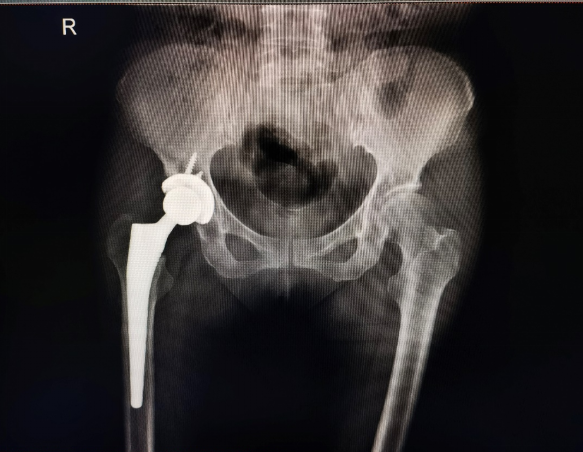

术后X线检查结果

吕松岑教授表示,通过机器人辅助手术系统,能够有效提高手术的精准性和安全性,让假体安放角度和位置更优,延长使用寿命,降低并发症的风险;其次,机器人手术系统能够减少医生的操作难度,提高手术效率;第三,通过术前CT扫描等检查,医生能够根据患者个体特征制定个性化的手术方案,实现更精确的手术操作;最后,该技术能够缩短患者康复时间,提高患者生活质量。(田为 曹玥 程实)